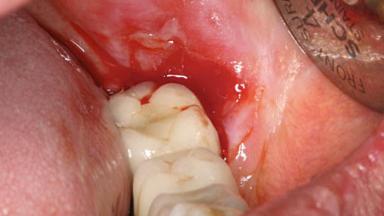

Oral Lichen Planus Associated with the Peri-implant Mucosa

This case describes the ongoing management of a 64-year-old healthy, non-smoking female patient with erosive oral lichen planus (OLP) affecting the gingivae and the buccal and lingual mucosa. The peri-implant mucosa was also affected subsequent to implant placement. The patient had osseointegrated implants (four in the maxilla, four in the mandible) placed following extraction of hopeless teeth and a healing period. The patient had a history of OLP prior to implant placement and had been referred to an oral-medicine specialist for definitive diagnosis and treatment. She exhibited generalized oral mucosal involvement. Following a clinical assessment, biopsy, and blood tests, she was treated with topical corticosteroids. Systemic prednisolone was reserved for severe flare-ups. Amphotericin lozenges were used in combination with corticosteroid treatment to prevent the development of oral candidiasis.